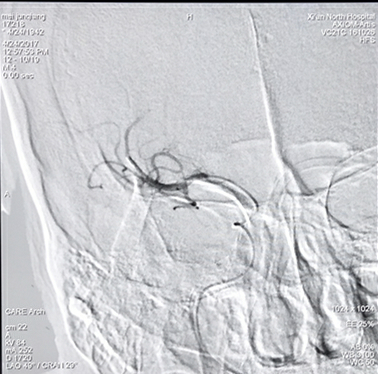

病例二:慢性颈动脉闭塞开通手术

反复左侧肢体无力,造影显示右侧颈动脉慢性闭塞。(下图)

实施颈动脉慢性闭塞开通后颈动脉完美再现,左侧肢体无力症状消失(下图)